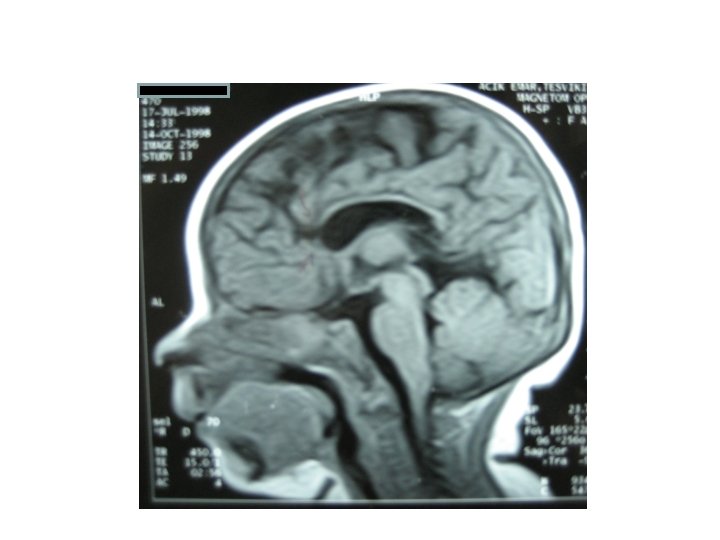

Radyoloji:

• Radiological assessment: Skull x rays, CT, MRI • IGF 1 measurement, physiological tests of GH secretion